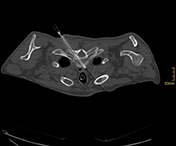

R20-Export_1_vs2 R20-Export_3_vs R20-Export_5_vs_2 R20-Export_7_vs

„Interventionelle Radiologie auf höchstem Niveau“: v.l.n.r: Biopsie einer Metastase eines Tumors der Speiseröhre durch die Wirbelsäule; Implantation einer vierfach verzweigten  Gefäßprothese in der Hauptschlagader zur Ausschaltung eines Aneurysmas; Biopsie eines Tumors in der Verzweigung des Hauptgallenganges mit zwei Biopsienadeln und die Biopsie eines Tumors in der rechten Lunge. (Bilder können durch anklicken vergrößert werden.)